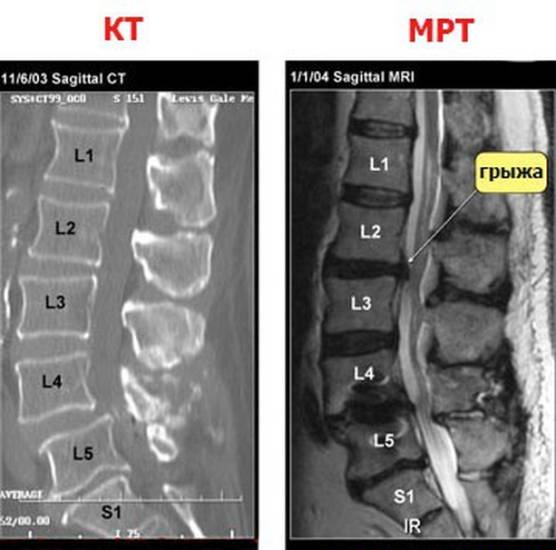

При боли в спине что лучше: КТ или МРТ

Пациентов, у которых болит спина, интересует вопрос — делать МРТ или КТ? Выбор диагностического метода остается за специалистом. Более безопасной считается магнитно-резонансная томография, так как во время исследования человек не подвергается облучению.

При острых травмах с повреждением тел позвонков рекомендуется сделать КТ, так как компьютерная диагностика лучше показывает костные ткани. Данный вид обследования применяют, если пациент не может длительное время сохранять неподвижность и при противопоказаниях к МРТ.

Когда нужно изучить состояние спинного мозга, сосудов, выявить наличие межпозвонковой грыжи, следует сделать магнитно-резонансную томографию, которая прекрасно визуализирует мягкие ткани.

В ряде случаев для изучения одной и той же области могут потребоваться сразу оба исследования.

Сравнение компьютерной и магнитно-резонансной томограмм